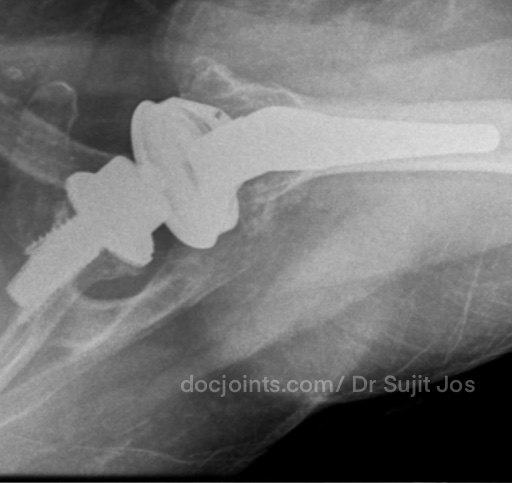

On presentation to the OP, the lifting power of the shoulder was significantly affected on strength testing (emply can test indicating supraspinatus tendon tear) and outward rotation was very weak (indicating Infraspinatus tendon tear). Xray and MRI images attached below.

There was significant fatty infiltration of the rotator cuff muscles along with osteoarthritis of the shoulder joint. Treatment options were discussed. Reverse shoulder arthroplasty is the modern treatment for this type of pathology, which can restore muscle function by orienting the shoulder centre of rotation in such a way that the Deltoid muscle can help in elevating the limb from neutral position (Read more about Reverse shoulder replacement >>).